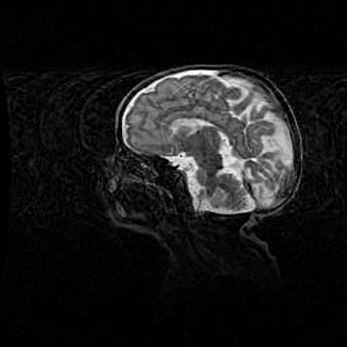

Церебральная ишемия II.

Возраст: 5 дней

Вес: 3400 г

Пол: женский

Окружность головы: 35 см

Срок гестации: 39 недель

Церебральная ишемия – это заболевание, характеризующееся недостаточностью (гипоксией) либо полным прекращением (аноксией) снабжения мозга кислородом по причине закупорки одного или нескольких сосудов. Это приводит к  что метаболическим расстройствам различной степени тяжести в тканях головного мозга, развитию коагуляционных некрозов и гибели нейронов.